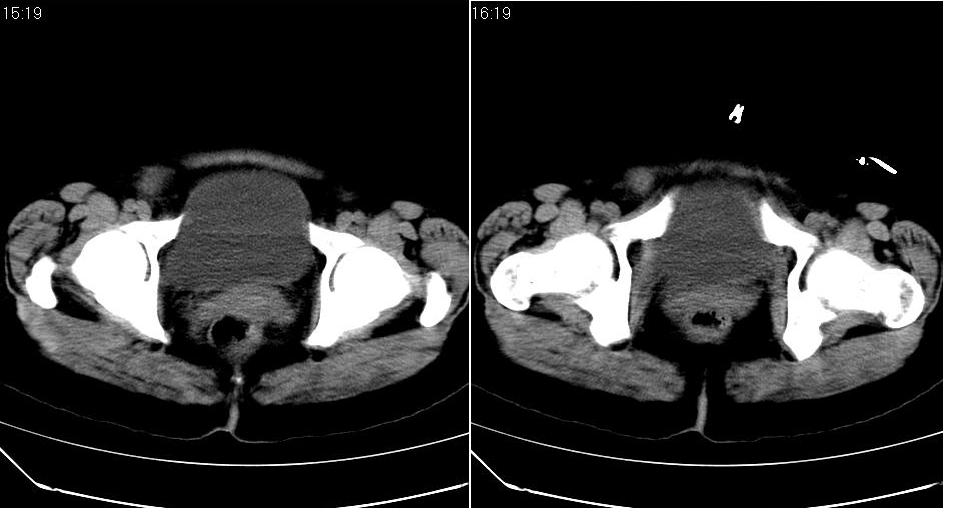

标题: CT17773B盆腔CT平扫

女 44岁,于ct17773号病例同一个病人。有结果我会尽快告诉大家。

盆腔及腹腔积液,原因待查。